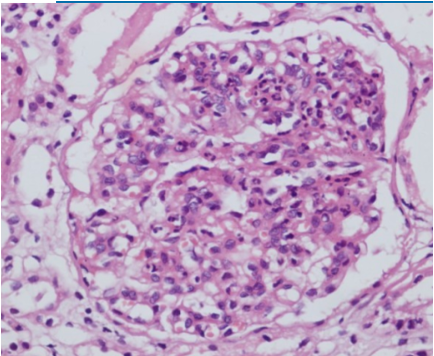

Diffuse proliferative glomerulonephritis

45 year old African American female presents to office with blood in her urine. She has no significant past medical history. Family history reveals sarcoidosis in her mother. Vital signs reveal BP 155/90. Lab studies reveal proteinuria (2.4 g protein), positive anti-double stranded DNA antibodies, and low complement C3 and C4 levels. An US-guided biopsy was performed. A tissue section representative of the remaining tissue is shown in the exhibit. The most likely diagnosis is: